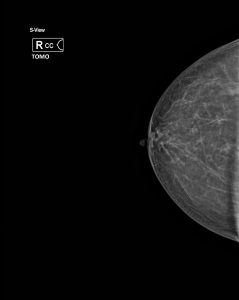

In unserer Praxis werden ausschließlich 3 D Mammographien ( Tomosynthese ) durchgeführt. Unter Tomosythese versteht man eine Schichtuntersuchung der Brust, wobei die vielen Einzelbilder zu einem 3 D Datensatz zusammen gerechnet werden. Dadurch ist eine wesentlich genauere Diagnostik und Früherkennung von Brustkrebs gewährleistet, was auch in entsprechenden wissenschaftlichen Arbeiten belegt ist.

Routinemäßig werden von jeder Brust Aufnahmen in 2 Ebenen angefertigt, bei Bedarf Zusatzaufnahmen. Um eine gute Bildqualität zu erzielen und die Strahlendosis niedrig zu halten, ist es notwendig, die Brust während der Aufnahme zu komprimieren. Dies kann als unangenehm empfunden werden, sollte jedoch nicht schmerzhaft sein. Da die Kompression im allgemeinen während der ersten Zyklushälfte als am wenigsten unangenehm empfunden wird, sollte die Untersuchung nach Möglichkeit entsprechend geplant werden. Der günstigste Zeitpunkt ist der 7. – 14. Tag nach Beginn der letzten Regelblutung.